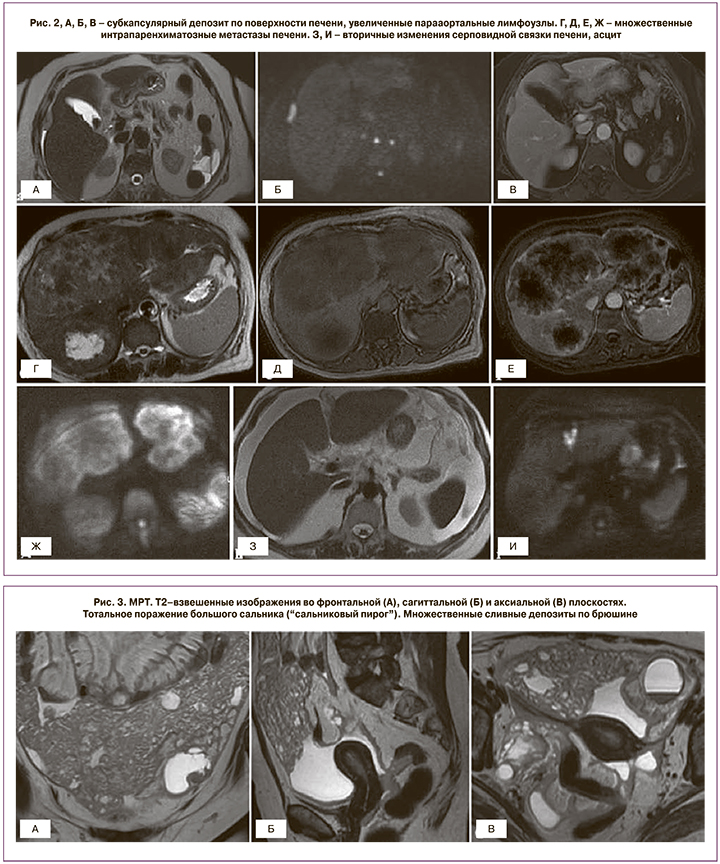

Локализация и размеры метастазов в печень должны быть четко задокументированы (рис. 2). Удаление интрапаренхиматозных метастазов, депозитов на уровне гепаторенального пространства (кармана Моррисона), нижней полой вены, правой печеночной вены может вызвать массивное кровотечение. Наличие вторичных изменений серповидной связки печени, ямки желчного пузыря, перипортального пространства более 2 см является предиктором неоптимальной циторедукции [28]. Удаление субкапсулярных депозитов печени, как правило, не вызывает сложностей.

Признаки поражения большого сальника варьируют от тяжистой исчерченности жировой клетчатки до многоузловых или сливных депозитов с формированием «сальникового пирога» (рис. 3).